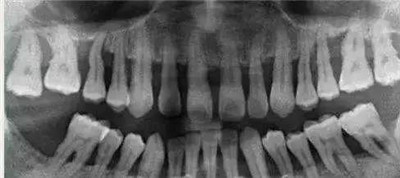

②牙龈炎没有骨的破坏,所以X线片上没有骨吸收的情况。而牙周炎X线片上可见牙槽嵴的高度降低,呈水平型吸收,也可出现近牙根面的牙槽骨吸收,呈垂直或角形骨吸收,这种骨的吸收,临床上表现为骨下袋。